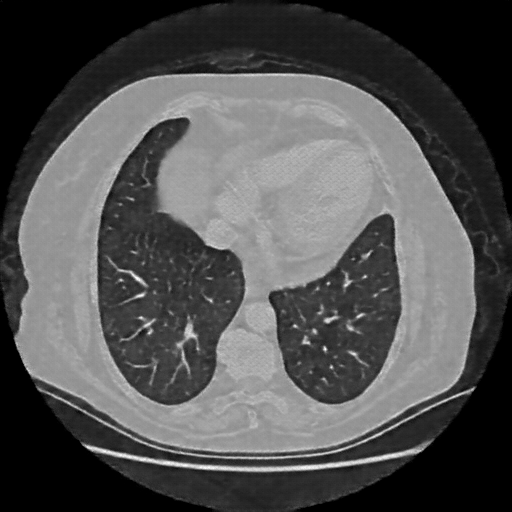

Original VENOUS CT scan

Full window (WL 1023.5, WW 4095 β†’ Low βˆ’1024, High +3071)

Lung window (WL -600, WW 1500 β†’ Low βˆ’1350, High +150)